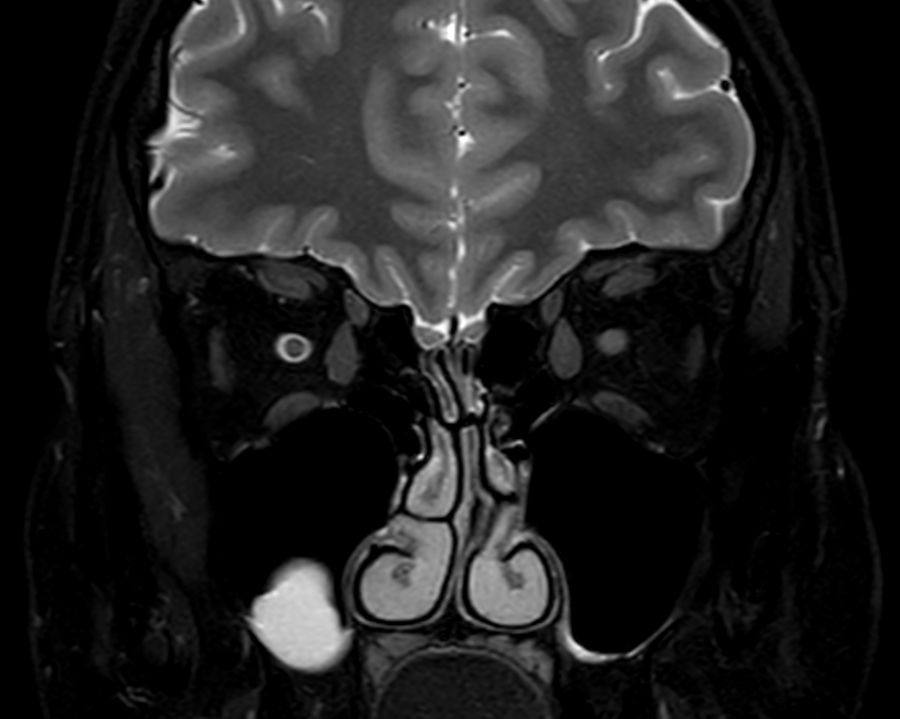

3D VIEW - T2w FatSat (coronal reformat)

Coronal T2w TSE mDIXON (In-Phase)

Coronal T2w TSE mDIXON (Water only)